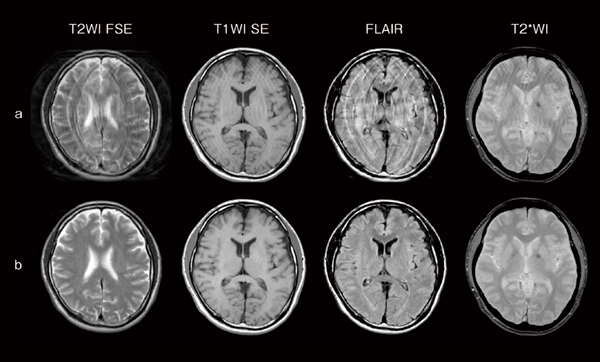

再撮像の頻度低減を支援するサポート機能

前述のSynergy Visionで被検者の体動を検知し,体動アーチファクトが画像上に確認された場合には,体動による画質劣化を改善する機能「Visual StillShot」を使用することにより,体動の影響がある受信信号を除去して画像を再構成できます。図2に頭部MRIのさまざまなコントラストを示していますが,体動アーチファクトが発生した画像を撮像後,Visual StillShotで再構成することにより,体動アーチファクトを低減した画像を生成することできるため,再撮像頻度の低減が期待できます。

図2 体動アーチファクト画像(a)とVisual StillShotによる再構成画像(b)

体動アーチファクトが発生した画像(a)を撮像後,Visual StillShotで画像再構成をすることにより,体動アーチファクトを低減した画像(b)を生成することができる。